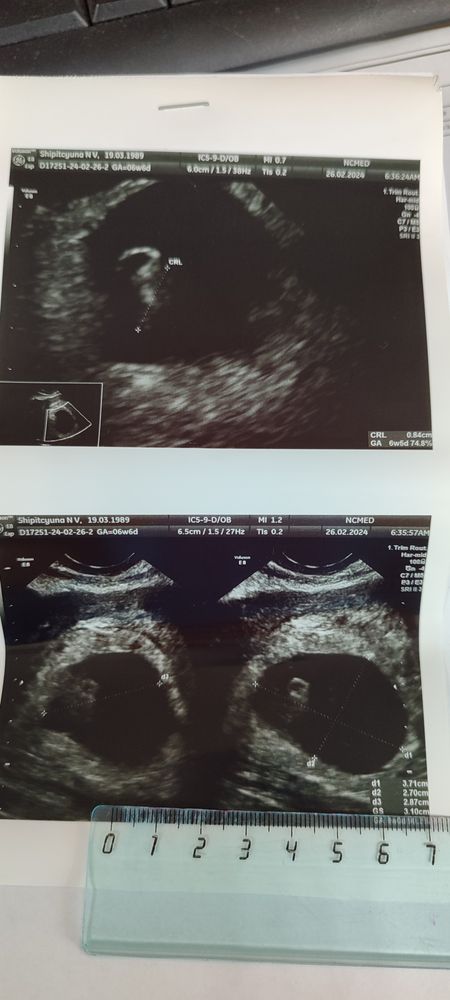

Узи 6,5 …Или 7,5 нед

Результаты: УЗИ, КТГ, доплера, скринингаСегодня сходила на узи, смущает такое большое плодное яйцо 🙈

Соответствует сроку 6,5 недель по месячным 7,5.

Сердцебиение +138у/м

плодное яйцо одно

Желточный мешок 3 мм

Ктр 8мм

Кольцевидная

С гипоэхогенным округлым образованием (желтое тело) 20мм

Вроде все нормально, но на фото плодное яйцо такое большое а эмбрион такой мааленький 🙈 чувствую через две недели еще пойду на узи, очень переживаю.